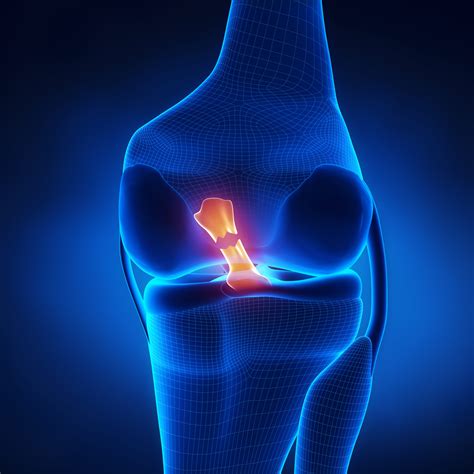

Receiving a diagnosis of a Post Cruciate Ligament Tear—commonly referred to as a PCL injury—can be a daunting experience for athletes and active individuals alike. Unlike the more frequently discussed ACL injury, the posterior cruciate ligament is the strongest ligament in the knee, requiring significant force to become damaged. Because it is responsible for preventing the shinbone from sliding backward under the thighbone, its injury can profoundly impact your stability, range of motion, and ability to perform daily activities. Understanding the nature of this injury, how it is managed, and the rehabilitation process is essential for navigating the road to recovery effectively.

The PCL is situated in the back of the knee, connecting the femur (thighbone) to the tibia (shinbone). A Post Cruciate Ligament Tear typically occurs due to a direct blow to the front of the knee while it is bent, often referred to as a "dashboard injury" because it frequently happens during car accidents. Other common mechanisms include falling onto a bent knee in sports or experiencing extreme hyperextension. Recognizing the severity is the first step toward treatment: